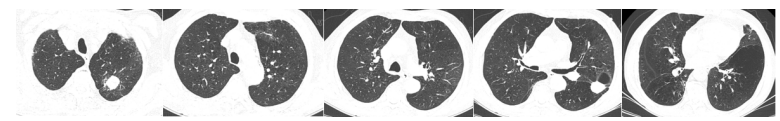

2023年10月10日随访胸部CT病灶仍在继续吸收(图7)。艾沙康唑口服两性霉素B雾化qd。11月13日胸部CT示左下肺病灶基本稳定(图8)。

家属对手术有顾虑,没有选择手术方案。后续治疗仅保留两性霉素B雾化。因为考虑患者肺部病灶内有菌丝或活性真菌存在,所以不能定义为完全缓解,只能定义为部分缓解。如果穿刺可获得病原学证据。